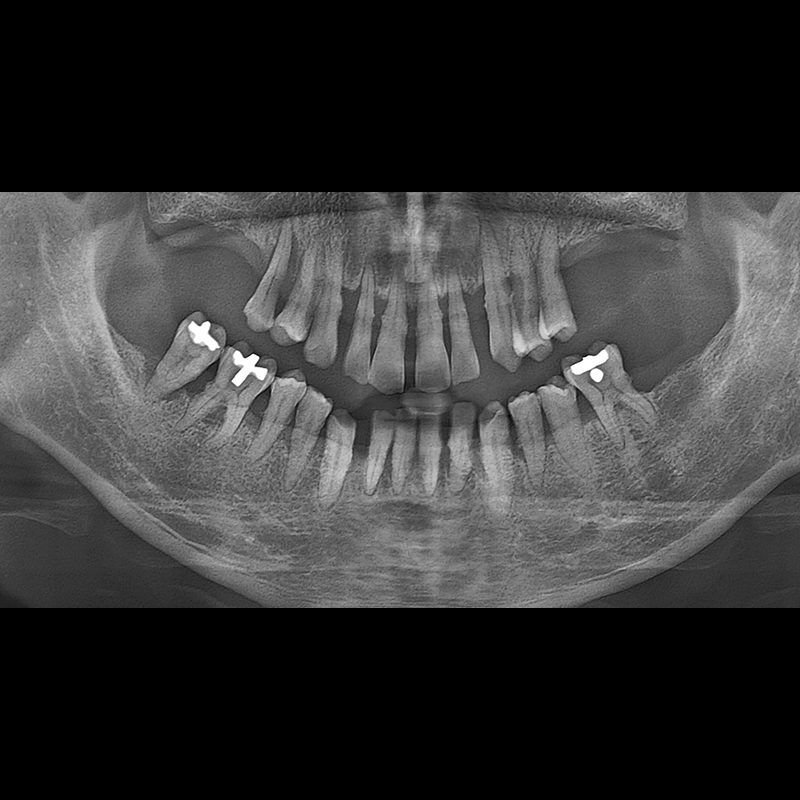

IMPLANT

BEFORE AFTER

임플란트 전후사진 2025.05.30

결손된 치아 부분과 살리기 힘든 치아 위치에 임플란트를 식립하였습니다.